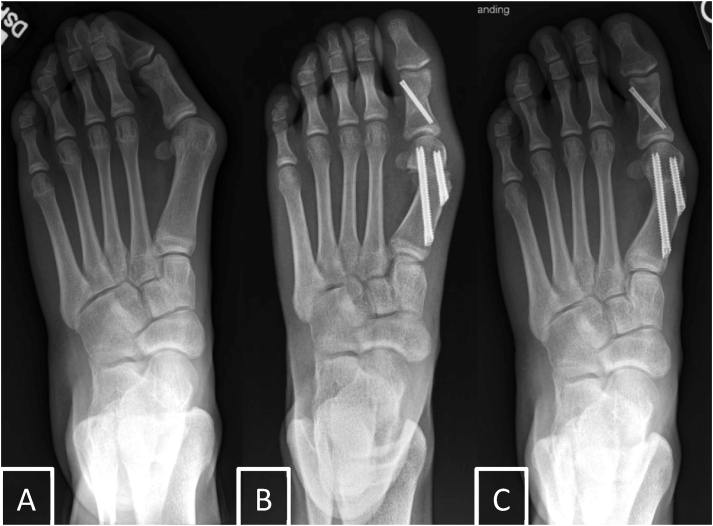

Abstract Image